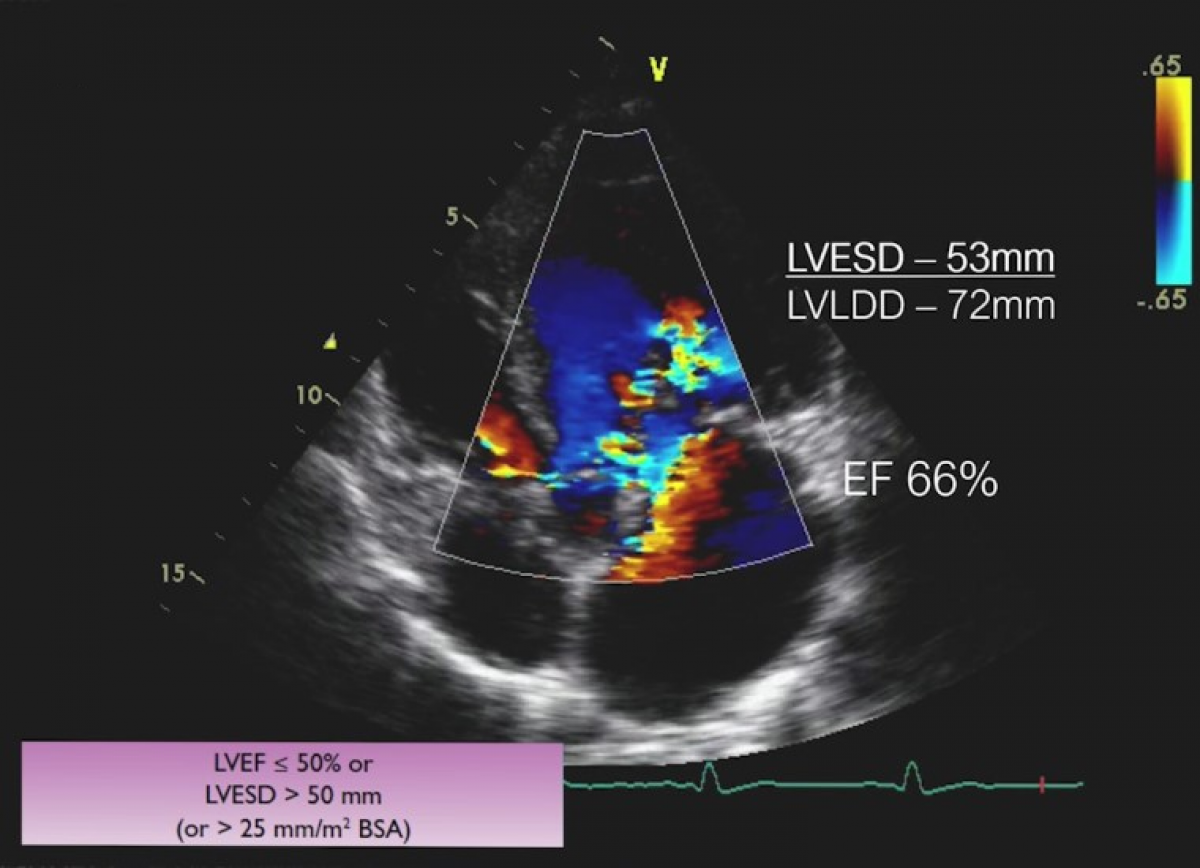

Ciężka niedomykalność aortalna na tle dwupłatkowej zastawki aortalnej.

Ocena niedomykalności aortalnej.

Ocena aorty piersiowej.